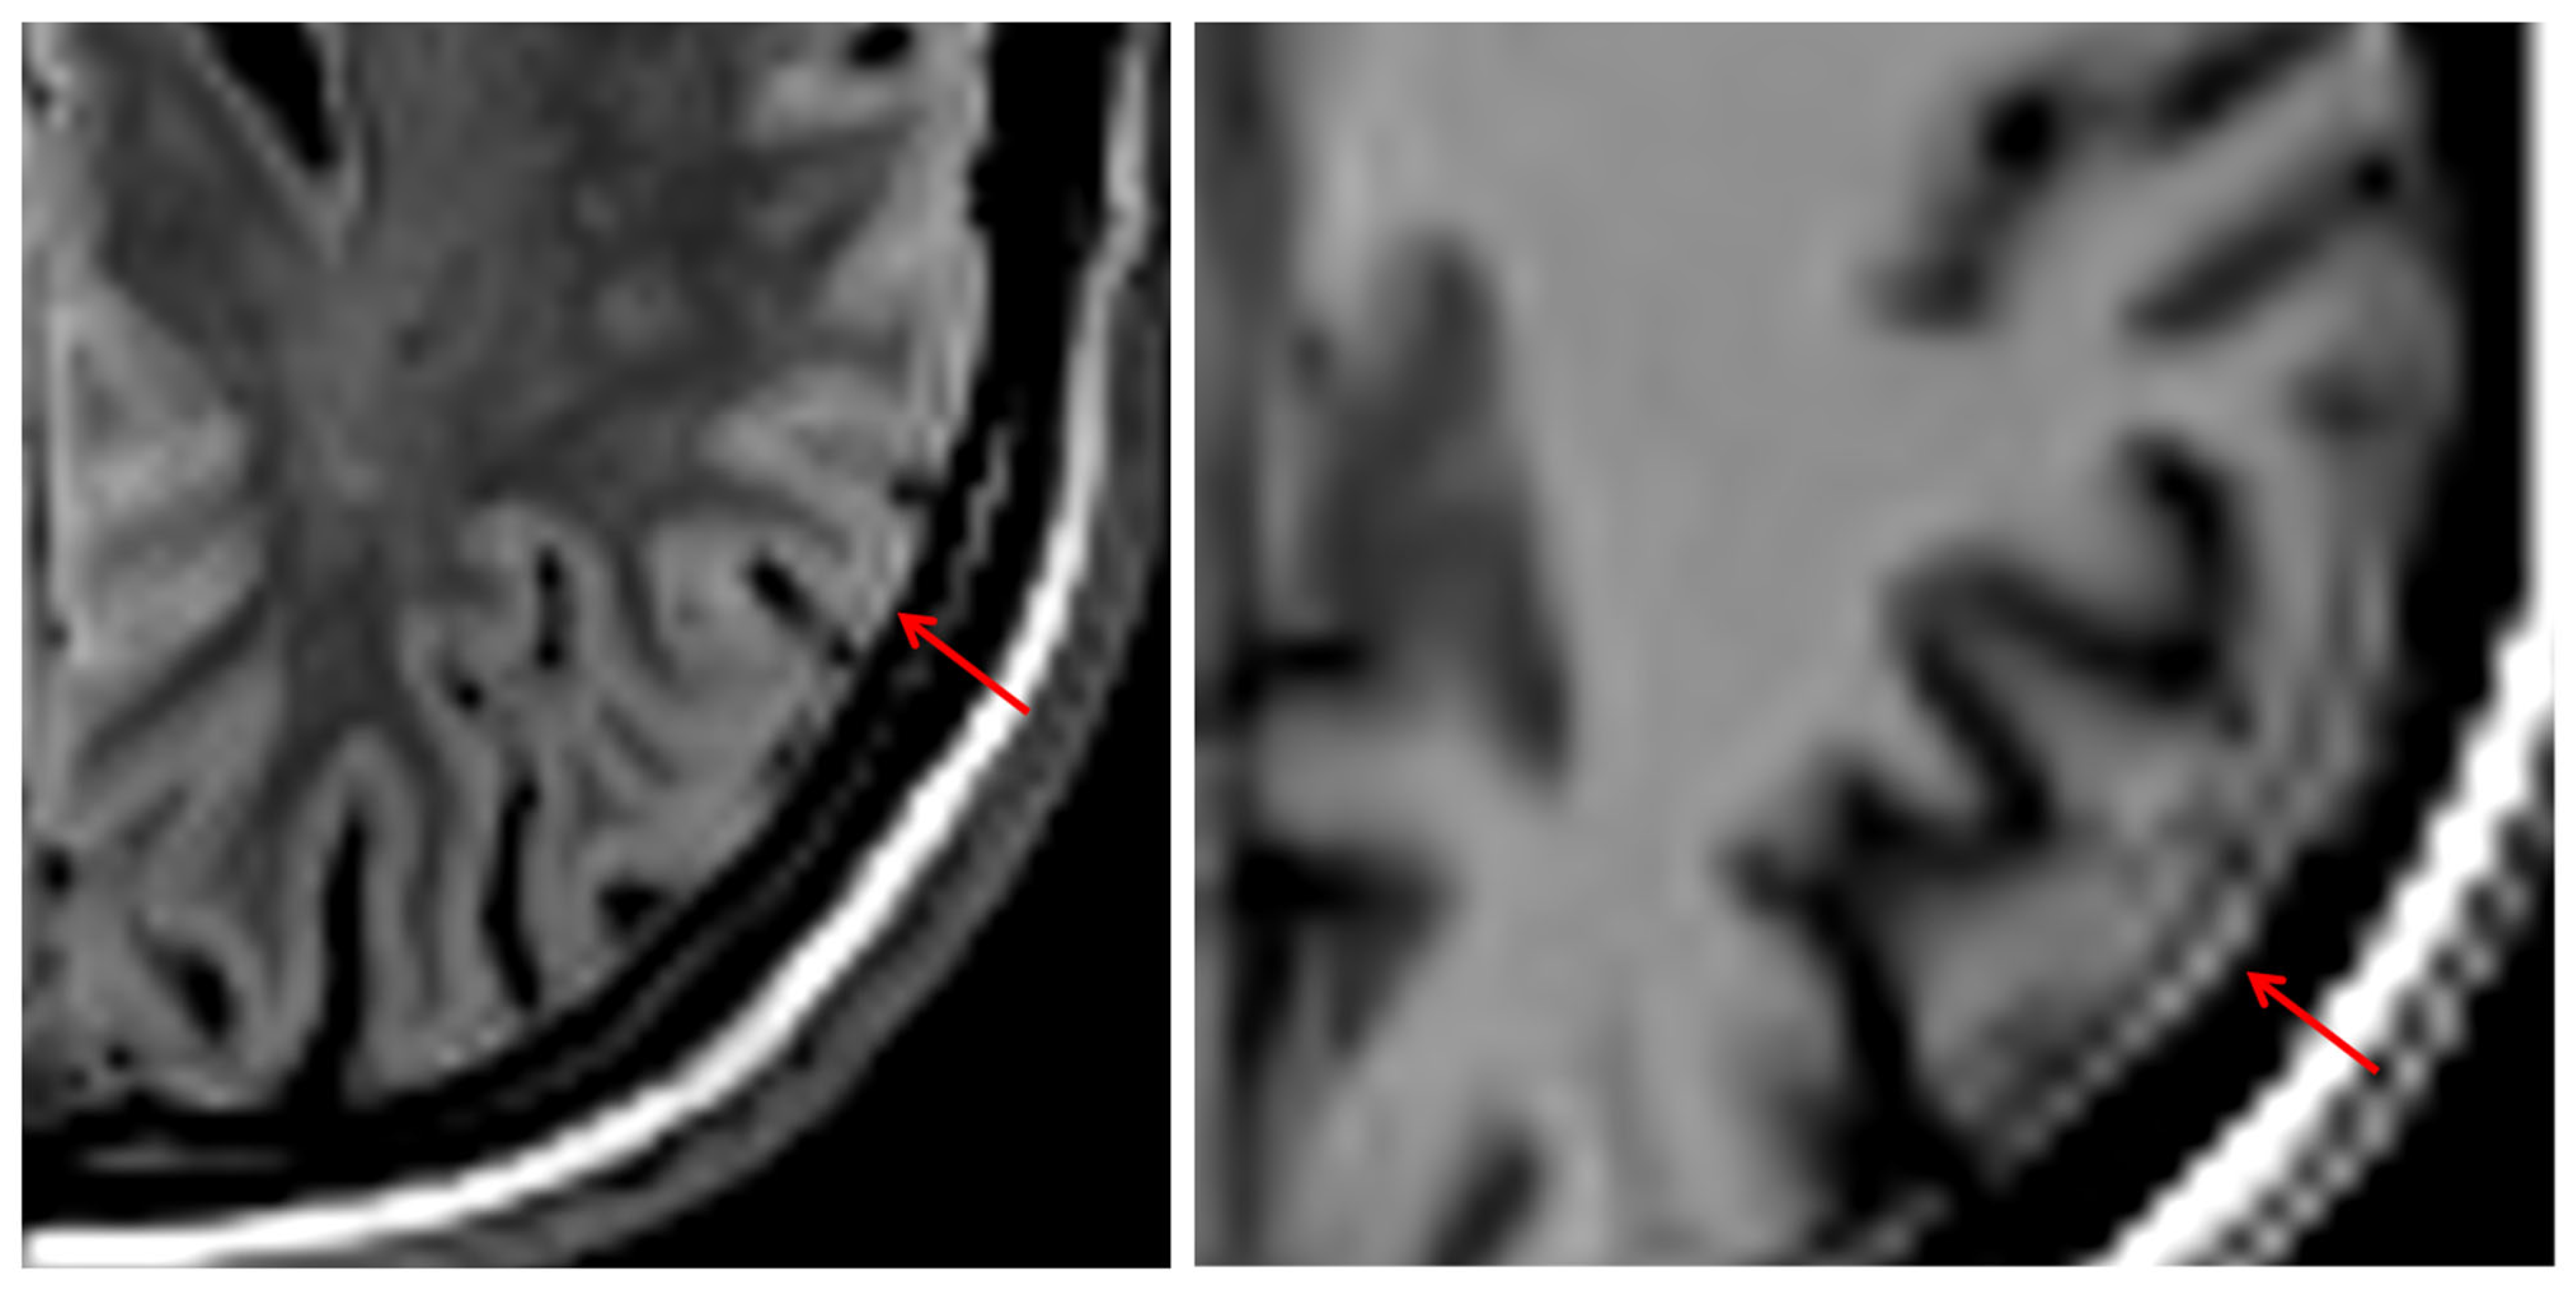

Of note, we found a thin hyperintense rim without echo contour on all 3D SI images, which delineated the surface of the brain. Figure 11 demonstrates this on a 3D SI FLAIR and T1w image. It is readily recognizable as an artifact, because it crosses anatomic borders.

The hyperintense rim at the cortical surface, visible in all 3D SI weightings and previously reported by Blystad et al. [26] and described as “ringing artifact” by Fujita et al. [7], complicates confident detection of cortical, subdural, and dural lesions. While this artifact is recognizable and, once familiar, may not degrade interpretive quality, its presence must be acknowledged to avoid diagnostic missteps, such as misinterpreting dural thickening or subdural hematomas.

Figure 11. Hyperintense rim at the outer border of the cortex and dura in T1w 3D SI.